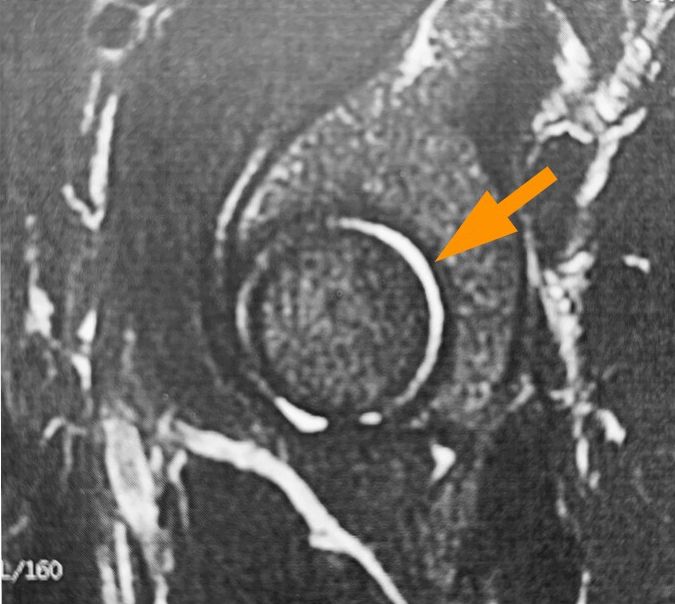

Basics CT scans are no longer of much use, except for surgeons. 3D models can help plan bone reconstructions, if necessary. Only special performed high resolution MRI images in the coronary, axial, sagittal and radial planes are sensitive enough and useful (30). A simple MRI of the pelvis will risk completely overlooking the problem and, in the worst-case scenario, send the patient home with a diagnosis of a normal hip. The MRI scan of the hip must therefore be conducted using special protocols that very few centres have as a routine.

It is often easier to order an arthrography, possibly with injection of an anti-inflammatory. Examinations using intra-articular contrast material (CT scan or MRI) reveal a thin-walled capsule, which readily takes up lots of contrast, and a distinct crescent sign with collection of fluid at the posterior joint indicating anterior subluxation (Fig. 1). If the patient has already undergone arthroscopy of the hip, there may be residual signs of the surgery. The labrum and cartilage must be examined carefully, but it should be noted that labral damage can be easily missed or underestimated by an arthrogram. Specificity can be improved by placing the hips under traction during the procedure, but this is never actually done, even when requested (30).